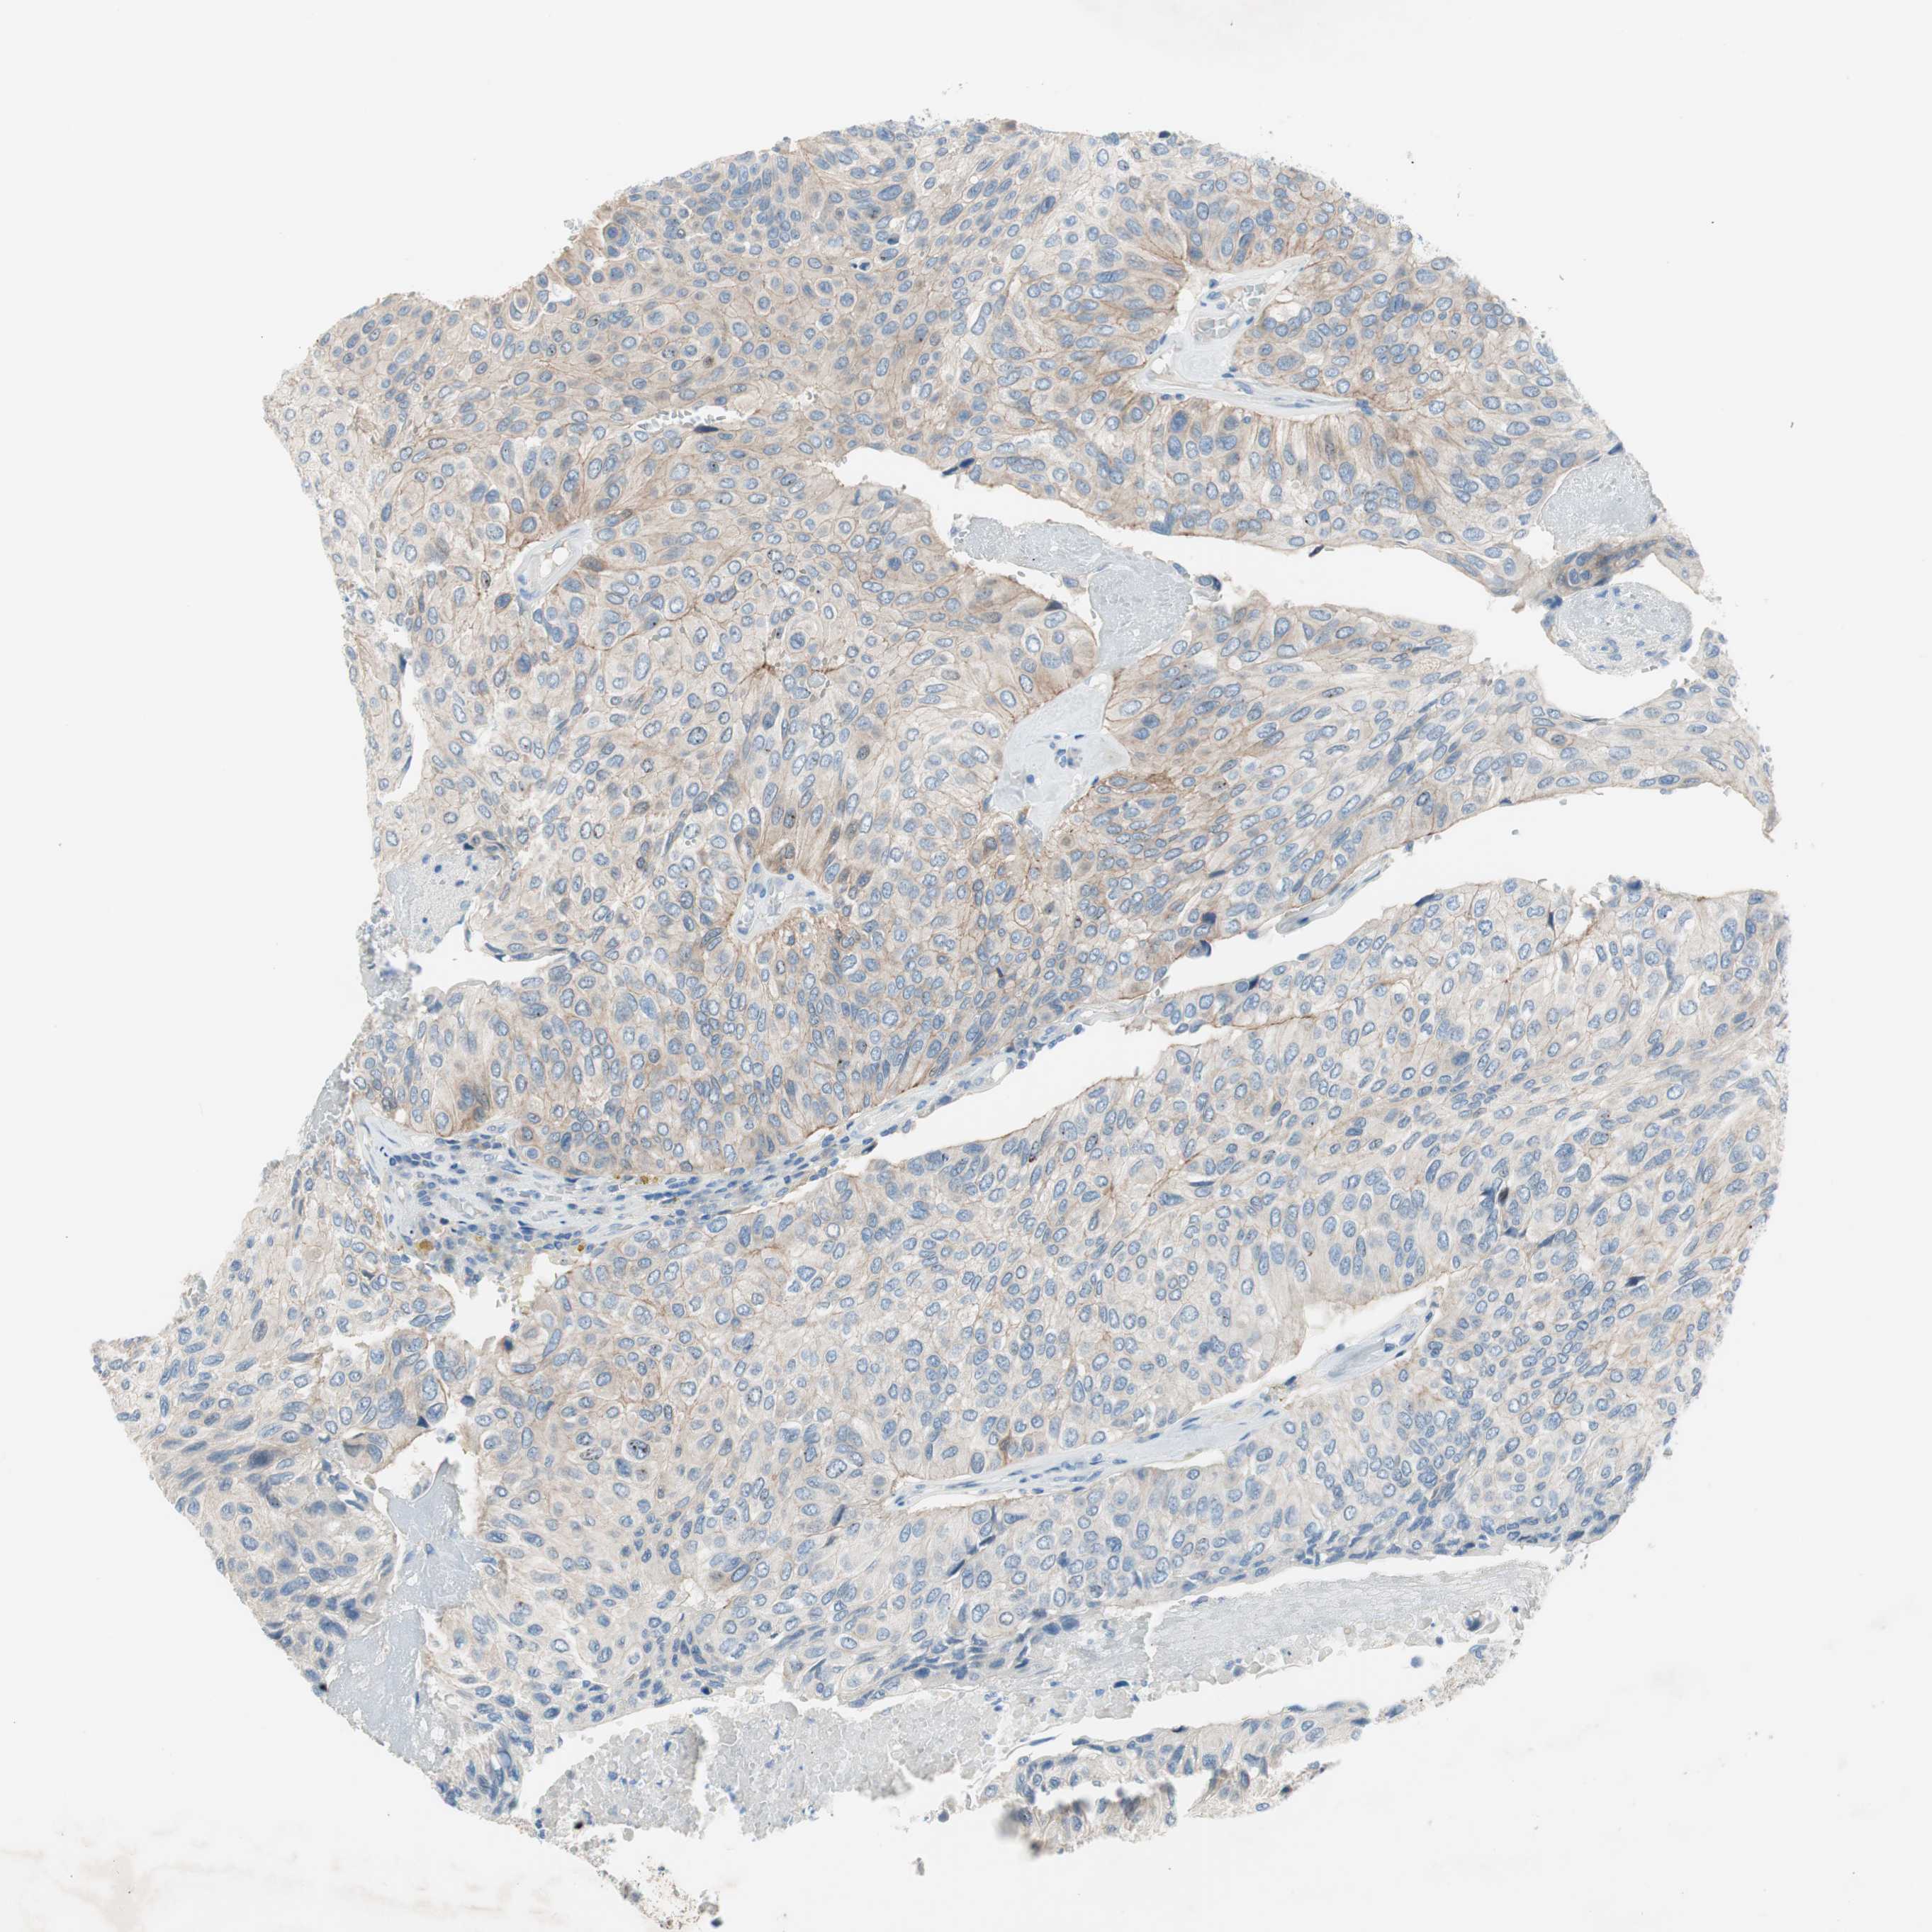

UROTHELIAL CANCER - Protein expressioni

A mouse-over function shows sample information and annotation data. Click on an image to view it in a full screen mode. Samples can be filtered based on level of antibody staining by selecting one or several of the following categories: high, medium, low and not detected. The assay and annotation is described here.

Note that samples used for immunohistochemistry by the Human Protein Atlas do not correspond to samples in the TCGA dataset.

Antibody stainingi

Antibody staining in the annotated cell types in the current human tissue is reported as not detected, low, medium, or high, based on conventional immunohistochemistry profiling in selected tissues. This score is based on the combination of the staining intensity and fraction of stained cells.

Each image is clickable and will lead to virtual microscopy that enables deeper exploration of all samples and also displays staining intensity scores, fraction scores and subcellular localization as well as patient and tissue information for each sample.

Antibody HPA009040

Antibody HPA024566

Staining

High

Medium

Low

Not detected

Intensity

Strong

Moderate

Weak

Negative

Quantity

>75%

75%-25%

<25%

None

Location

Nuclear

Cytoplasmic/membranous

Cytoplasmic/membranous,nuclear

Urothelial carcinoma, High grade